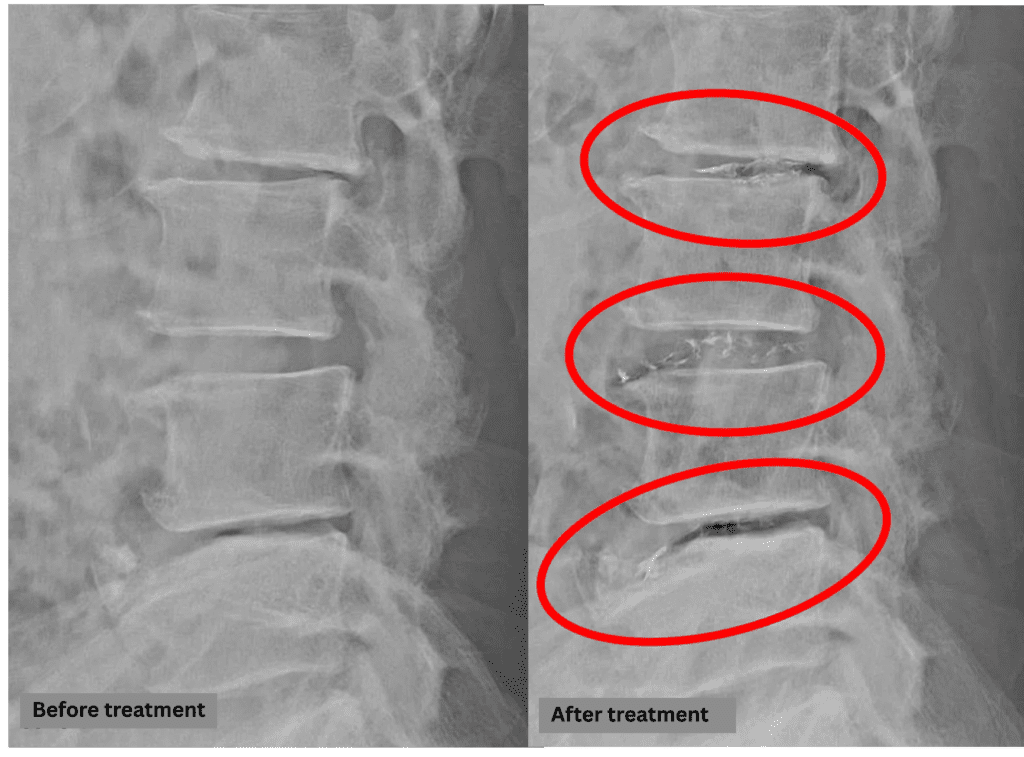

- L2/3: Disc degeneration, disc bulging, foraminal stenosis, spinal canal stenosis post-surgery

- L3/4: Disc degeneration, disc herniation, foraminal stenosis, spinal canal stenosis post-surgery

- L4/5: Disc degeneration, disc herniation, foraminal stenosis, endplate degeneration

The above findings were also observed on the imaging.

Based on these findings, spinal canal compression due to disc pathology at L2/3, L3/4, and L4/5 was considered the most likely cause of the patient’s symptoms.

After consulting with the patient, the Cellgel Method was performed on L2/3, 3/4 and 4/5 .